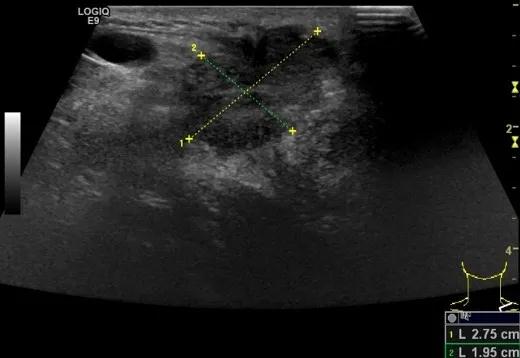

第四例是胸腺癌化妆包,术后、化疗之后淋巴结转移,肿块范围巨大,99mm*61mm,边界不清,呈浸润状,肿块包绕颈动脉,颈内静脉压闭,症状明显。由于患者放化疗也不敏感、血供非常丰富,于是采取多点姑息性消融。姑息性消融后未实现完全消融,病灶大片坏死,肿胀疼痛得到明显的缓解,后续患者未再来复查。

(病例4图例)